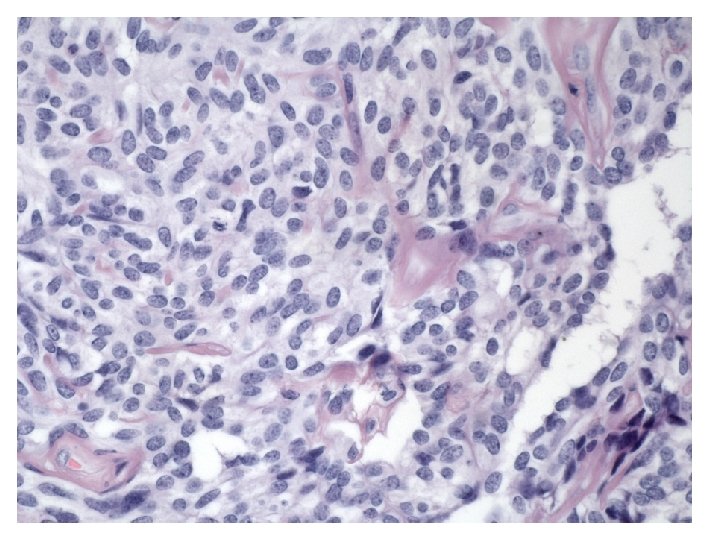

• Branching and anastomosing tubules: • Looks like:

• Looks sex-cord stromal • Looks like rete ovarii • With intraluminal thick eosinophilic secretions

Microscopy • Growth patterns: - Cystic or sieve-like (with eosinophilic secretions) - Tubular - Solid (sheets of cells or closely packed tubules) • Cells: - Epithelioid to fusiform - Pale to eosinophilic cytoplasm • Nuclei: - Round to oval with uniform chromatin - No or few mitotic figures